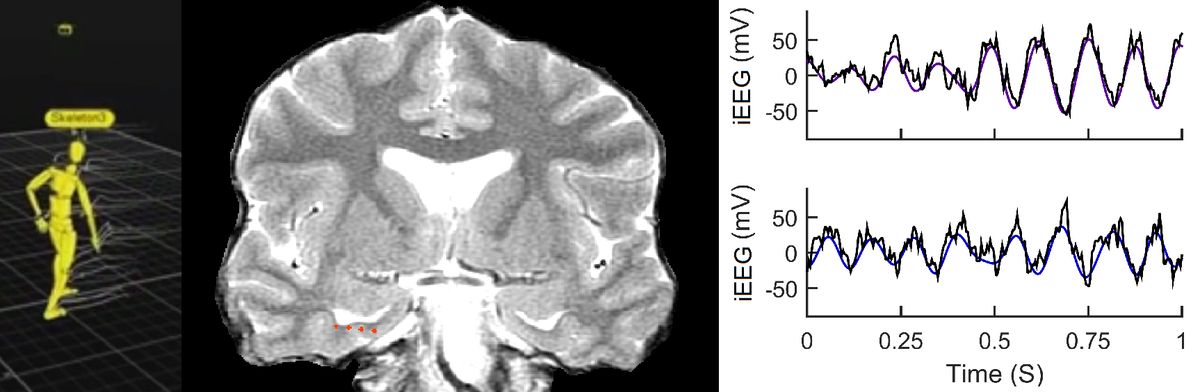

Real-time data downloaded from a patients wireless implant reveal the deep brain waves that support spatial navigation and memory.